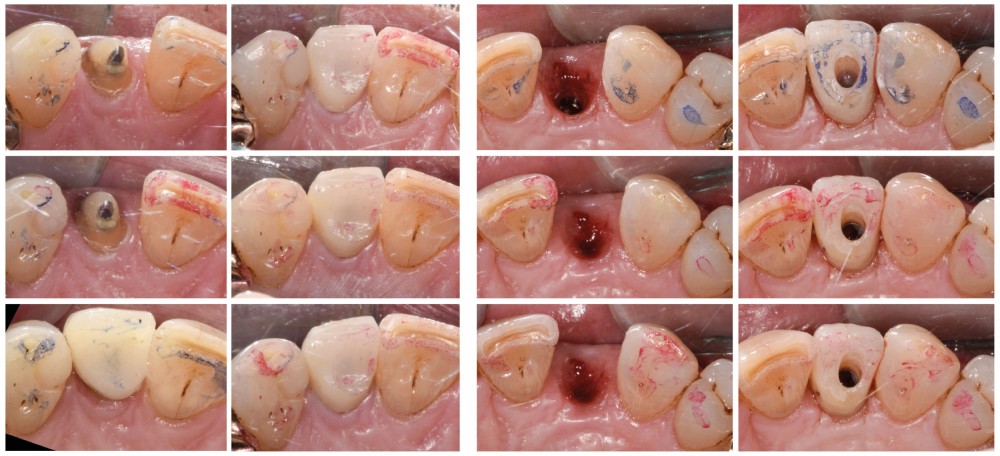

Situation initiale

Un patient de 62 ans se présente en consultation afin de réaliser les coiffes prothétiques des dents 12 et 22. La 12 présente une restauration par prothèse transitoire non adaptée. Un implant au niveau de la 22 a été posé par un autre praticien selon une technique chirurgicale en deux temps. Le praticien a adressé le patient pour la réalisation prothétique. L’option de bridge collé cantilever mono ailette n’avait pas été retenue ou proposée selon une technique chirurgicale en deux temps. Le patient souhaite rétablir l’esthétique et la fonction de ces deux dents uniquement.

Au vu des conditions initiales, il nous apparaît impossible de restaurer une esthétique satisfaisante, notamment au niveau de l’alignement des collets, sans une chirurgie muco-gingivale associée à une réhabilitation des dents antérieures par facettes. En effet, la perte de la 22, associée à une forme triangulaire des dents, a provoqué un non-alignement des collets ainsi que la présence de trous noirs entre les dents 21-22 et 22-23. Cependant, les contraintes exprimées par le patient contre-indiquaient ce traitement.

La proposition thérapeutique retenue par le patient est donc une réhabilitation par couronne céramique sur 12 (dento-portée) et 22 (implanto-portée). Ce choix thérapeutique impose de concevoir des dents qui s’intègrent au mieux dans l’harmonie du sourire, tout en étant conscient des limites d’un tel traitement.